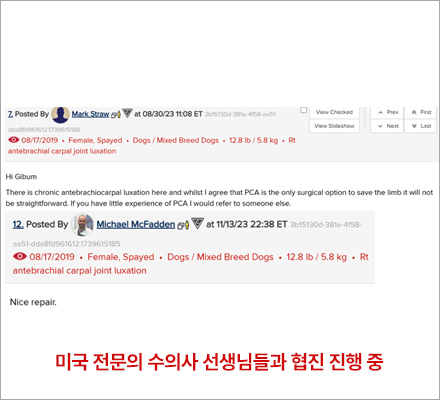

손목관절 만성 탈구

- 손목 관절고정, 고난이도 수술

- 5살, 5.5kg, 믹스견

일반적이지 않은 케이스의 경우 미국 전문의 수의사 선생님들과 협진 진행 중입니다.